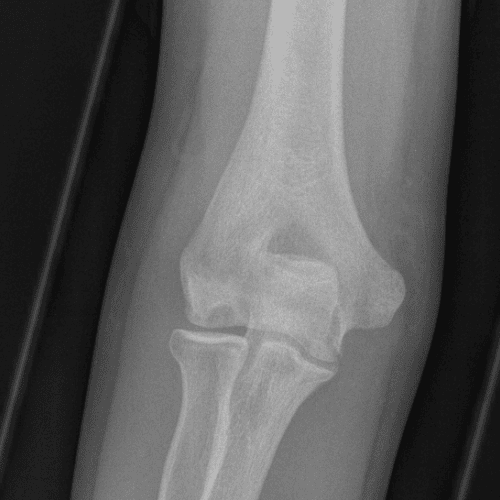

Simulates call by including subtle or difficult cases and some normals.

40 cases